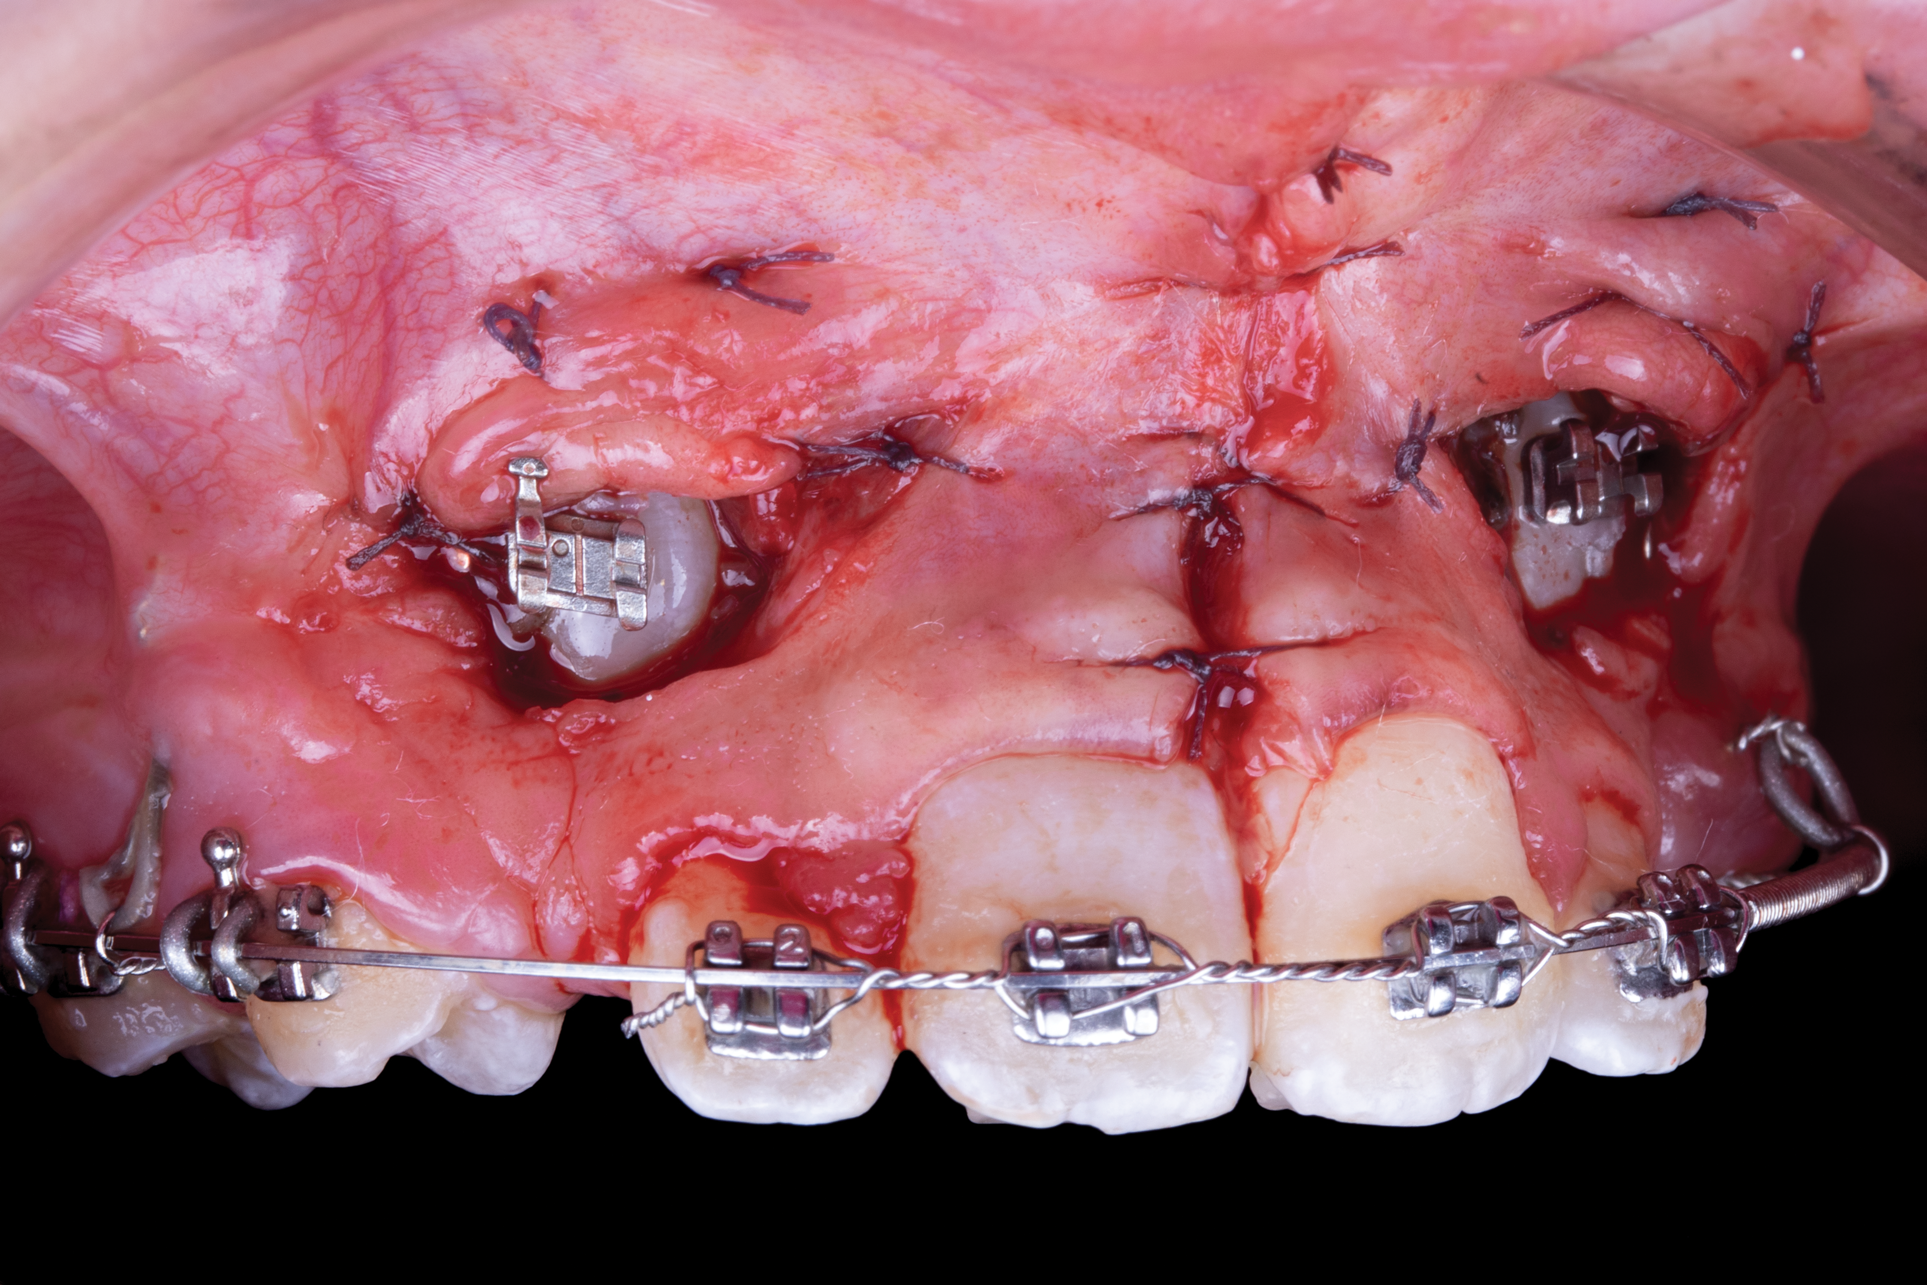

Apically repositioned flap-This technique is an option when there is not enough keratinized gingival tissue, and it is the preferred surgical procedure when the impacted canine is mesial to the lateral incisor.27,48 The flap must be secured and adapted to the tooth. Contraindication for this technique is risk of gingival recession and uneven gingival margin and the need for extensive osseous surgery.48 The flap is made by an incision with a 15 or 15c blade on the ridge to obtain the maximum amount of keratinized gingival tissue.27,45,48 Vertical incisions are performed, and the flap is moved in a lateral or apical direction.8 A flap design is recommended in which the base and the coronal zone are either the same width or narrower at the base, with a thickness of 4 mm to 5 mm, so the flap can be wide enough mesiodistally, extending 1.5 mm beyond the angle of the tooth (Figure 6 and Figure 7).8,35,36 Any bony shell covering the tooth should be removed with a curette or diamond bur to expose the coronal portion of the crown.8 The flap is then positioned at the CEJ and secured with periosteal sutures to obtain greater stability. Depending on the degree of canine impaction, a periodontal dressing can be placed so the tissue does not close.8,35,36 The bracket is placed either at the time of the procedure or 10 days after.35 If the impacted canine is too apical, the closed technique is performed.26,35 Generally, orthodontic movement begins 4 to 6 weeks after the surgical exposure.26 When a wide follicle surrounds the canine, the flap incision should be made wider than the follicle to permit optimum adaptation of the flap to the crown and bone. To determine if the flap is well adapted, when the lip moves the flap should remain stationary.8,35,36

Fig 6. Use of apically positioned flap to manage bilateral facially impacted canines. During the same procedure a midline frenectomy was performed after the exposure and bilateral brackets were placed (Fig 6). Orthodontic traction was performed, which allowed both canines to be properly placed in the upper arch (Fig 7).

Figure 6

Fig 7. Use of apically positioned flap to manage bilateral facially impacted canines. During the same procedure a midline frenectomy was performed after the exposure and bilateral brackets were placed (Fig 6). Orthodontic traction was performed, which allowed both canines to be properly placed in the upper arch (Fig 7).